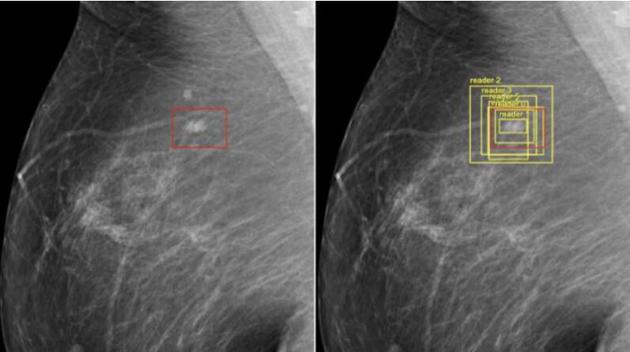

检测乳腺癌的谷歌人工智能

谷歌公司的研究人员已经成功训练出能够检测乳腺癌的人工智能,其准确率甚至比医生还高

在进军医疗领域的努力中,谷歌公司的研究人员已经成功训练出能够检测乳腺癌的人工智能,其准确率甚至比医生还高。在谷歌资助的这项研究中,一个由不同医院和大学的独立研究人员、谷歌健康部门的研究人员,以及DeepMind(谷歌拥有的英国人工智能公司)的工程师组成的团队,对来自英国和美国的近29000张乳房X光片进行了分析和比较。研究报告发现,美国和英国的假阴性结果分别减少了9.7%和2.7%,假阳性结果分别减少了5.7%和1.2%。这还是在人工智能处理的信息较少的情况下实现的。在其对照研究中,谷歌从其美国数据集中随机选择了500张X光片,并提供了患者的年龄、乳腺癌病史和之前的X光片。